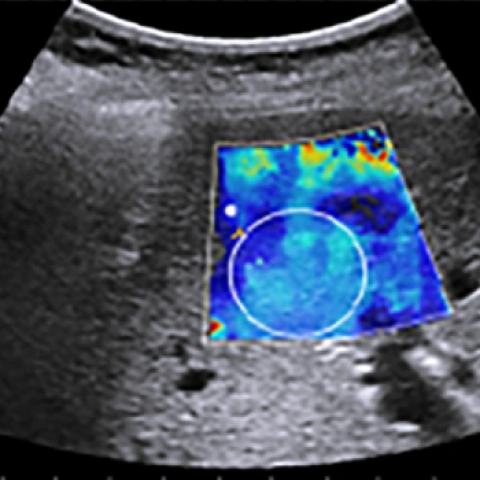

এই কারণেই তৈরি হয়েছে একটি বিশেষ পদ্ধতি যার নাম Shear Wave Elastography (SWE)। এই পদ্ধতিতে একধরনের ক্ষুদ্র কম্পন বা shear wave শরীরের ভেতরে পাঠানো হয়। এই তরঙ্গ পাশের দিকে ছড়িয়ে পড়ে এবং তার গতি (shear wave speed) থেকে বোঝা যায় টিস্যুটি কতটা শক্ত বা নরম। তরঙ্গ যত দ্রুত যাবে, টিস্যু তত শক্ত—এটাই মূল ধারণা।

তাই SWE হলো এমন এক non-invasive (অর্থাৎ অস্ত্রোপচার ছাড়া), real-time (অর্থাৎ সঙ্গে সঙ্গে দেখা যায়) এবং সাশ্রয়ী প্রযুক্তি, যা অনেক উন্নত দেশে চিকিৎসকদের নিয়মিত ব্যবহার্য।

এটি তৈরি করে একদম পরিষ্কার stiffness map, যা চিকিৎসকদের শরীরের ভেতরের কঠিন ও নরম অংশগুলো সহজে আলাদা করতে সাহায্য করে।